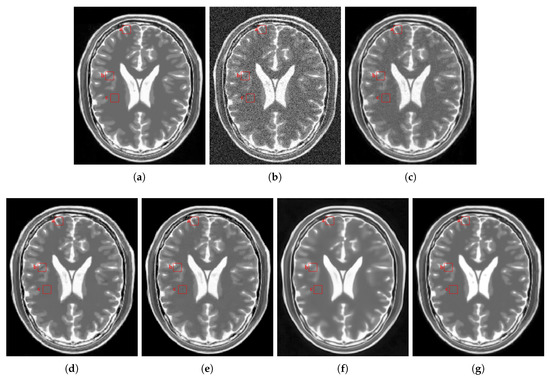

4.2.2. Real Data